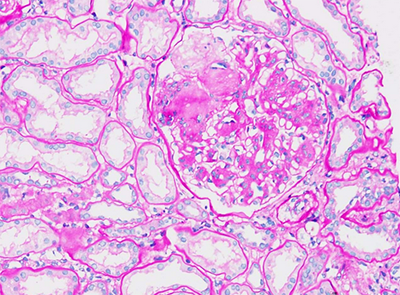

提供常规的石蜡切片、H&E染色诊断;

特殊染色-番红固绿染色.jpg特殊染色-PAS染色.png